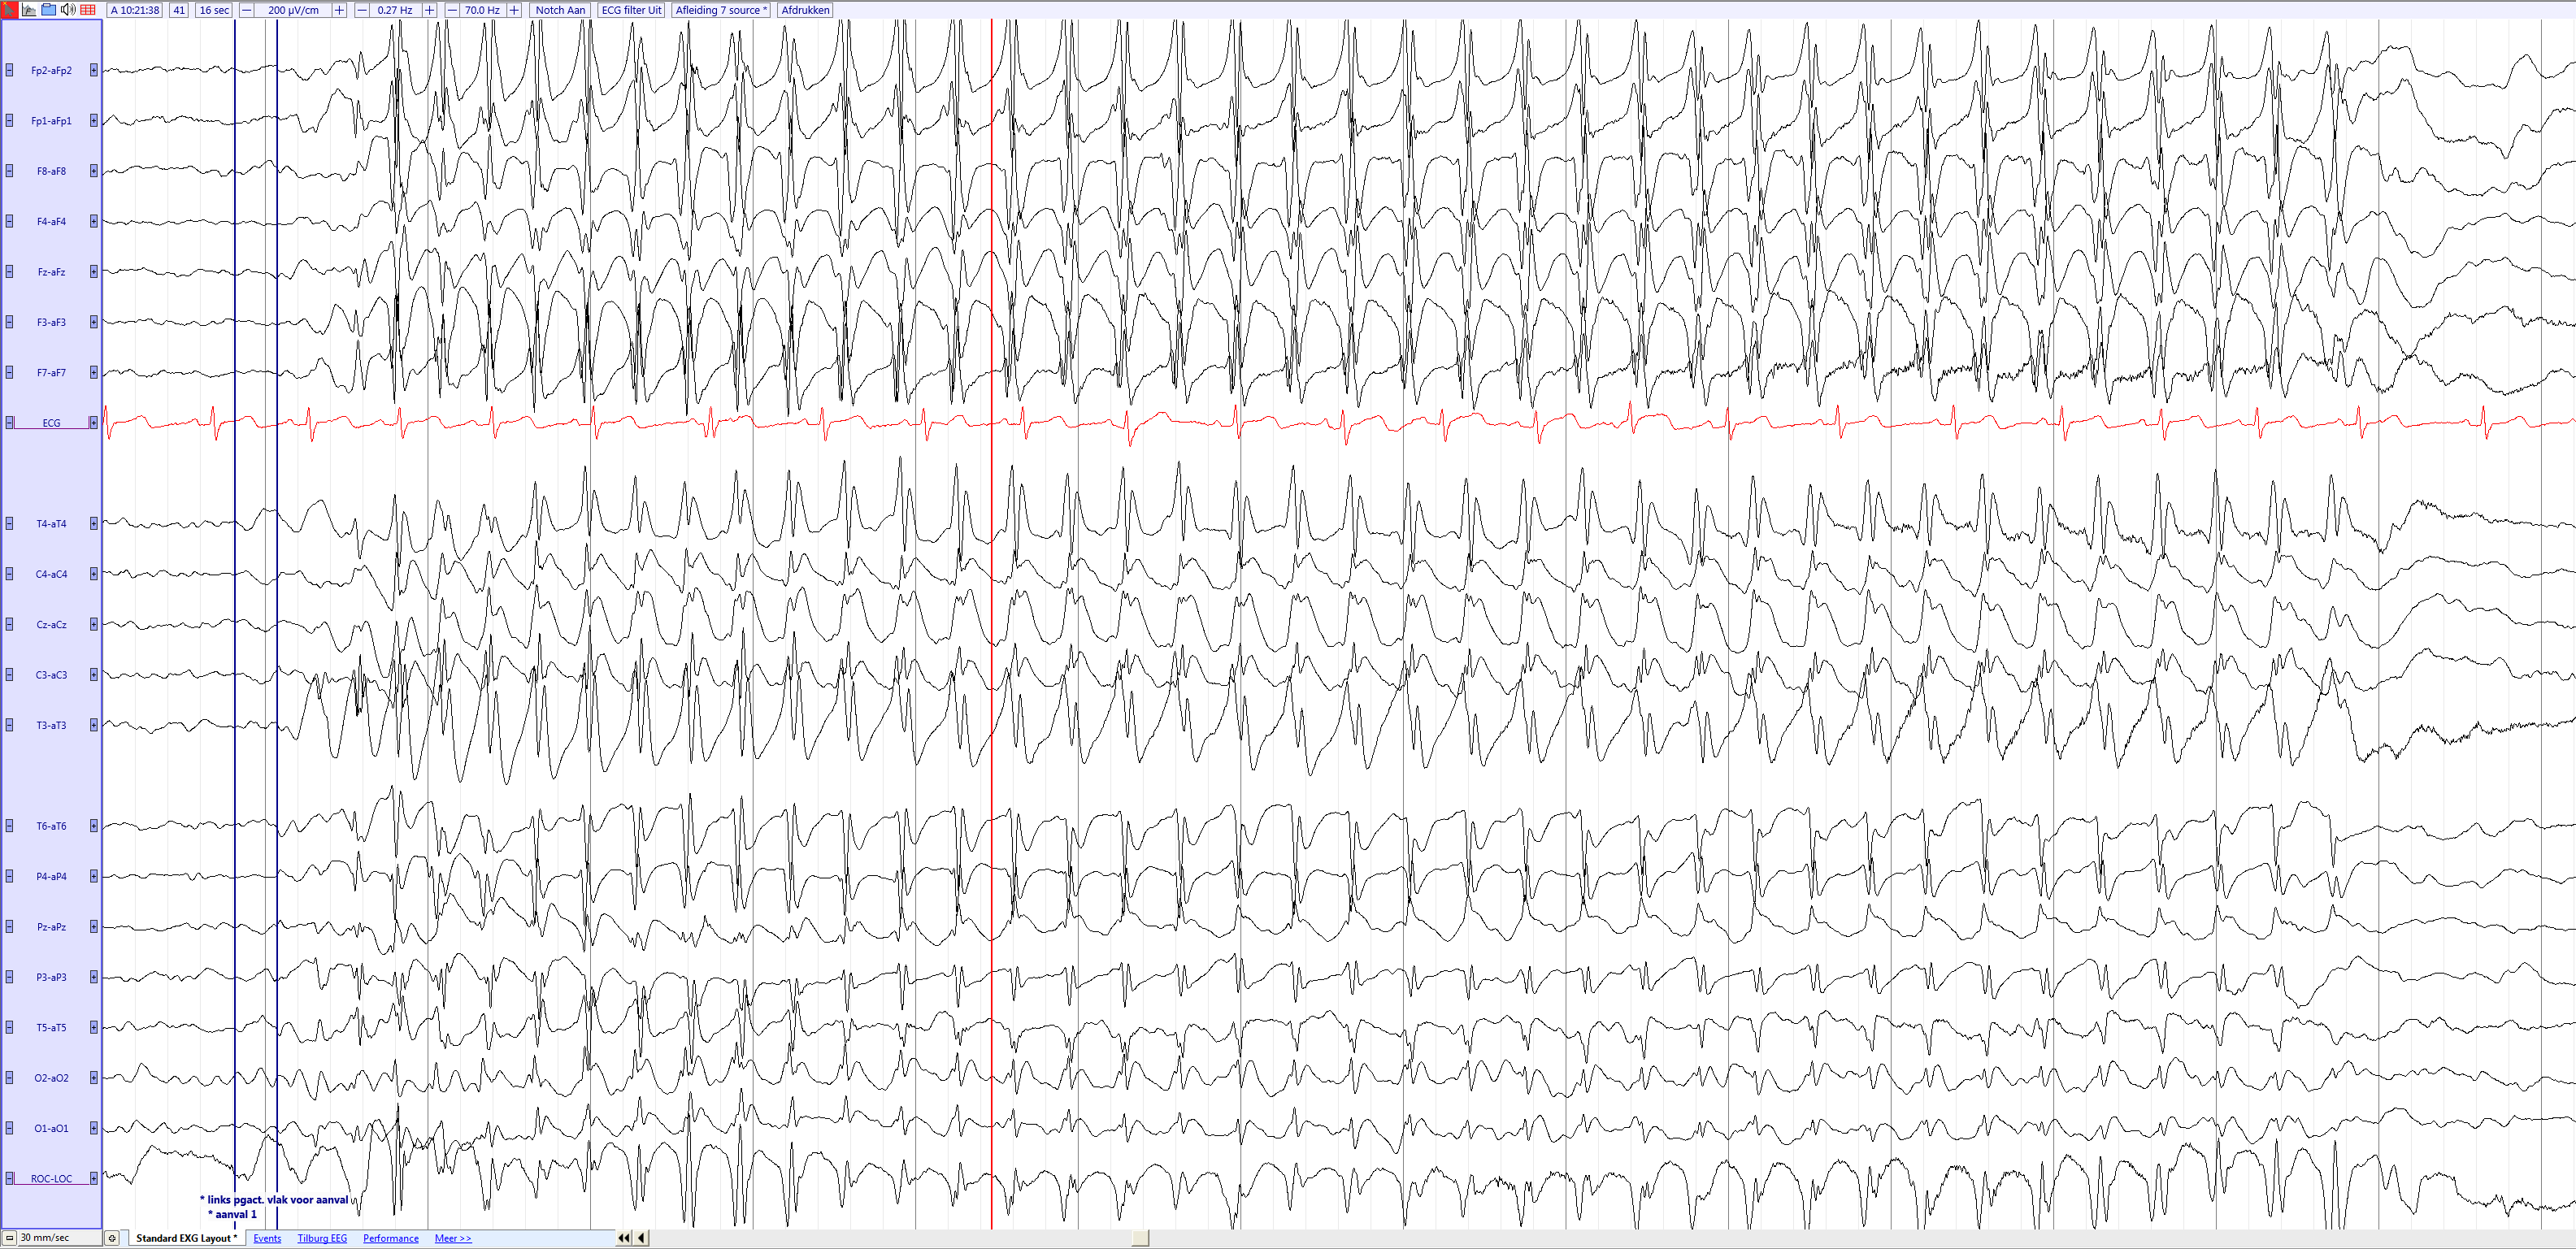

_EEGpedia.png)

File Childhood Absence Epilepsy 4 5 Year Old Girl source EEGpedia png